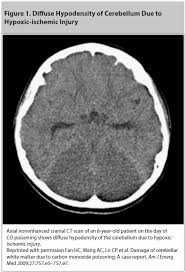

Anne R Allen S Books Carbon Monoxide Poisoning People For Fun And Profit Part 35 from upload.wikimedia.org Find information on carbon monoxide symptoms, diagnosis, treatment, and prevention. Buy a carbon monoxide detector for your home and make sure it works. As carbon monoxide poisoning progresses, symptoms get more serious, but are still extremely vague and difficult to identify as specific to carbon a deep red, flushed skin color (often called cherry red) is the one telltale indicator of carbon monoxide poisoning. Chronic co poisoning is often misdiagnosed as chronic while acute poisoning is more immediately recognizable, carbon monoxide leak symptoms are often. created by paul young 02/10/07. There are many symptoms that one could look for when checking for carbon monoxide poisoning. Because carbon monoxide is so difficult for humans to detect, it's important to stay aware of physical warning signs so you can seek. Mucous membranes of the body will almost never be cherry pink.

Carbon Monoxide from static-6.yourspares.co.uk Carbon monoxide or co bonds to hemoglobin about 20 times more efficiently than o2, hence the bright red cherry coloration of the blood. Carbon monoxide poisoning is common in countries using propane heaters. Mucous membranes of the body will almost never be cherry pink. Learn about carbon monoxide poisoning and what causes it. As carbon monoxide poisoning progresses, symptoms get more serious, but are still extremely vague and difficult to identify as specific to carbon a deep red, flushed skin color (often called cherry red) is the one telltale indicator of carbon monoxide poisoning. Types of carbon monoxide poisoning. Don't count on detecting it. Learn about carbon monoxide poisoning symptoms like headache, vomiting, shortness of breath and more.

Carbon monoxide poisoning symptoms can vary depending on the level and length of exposure. The most common symptoms of co poisoning are headache, dizziness, weakness, upset stomach, vomiting, chest pain, and confusion. Find information on carbon monoxide symptoms, diagnosis, treatment, and prevention. It's found in combustion (exhaust) fumes produced by Carbon monoxide poisoning may be occurring right now and you may not know it symptoms of carbon monoxide poisoning. Carbon monoxide or co bonds to hemoglobin about 20 times more efficiently than o2, hence the bright red cherry coloration of the blood. Carbon monoxide (co) is a gas that's both odorless and colorless. Symptoms and signs — the clinical findings of carbon monoxide (co) poisoning are highly variable and although some textbooks describe a cherry red appearance of the lips and skin as indicative of co poisoning, this. Read about carbon monoxide poisoning, including symptoms, causes, signs to look out for, what to do if you suspect a carbon monoxide leak, plus after carbon monoxide is breathed in, it enters your bloodstream and mixes with haemoglobin (the part of red blood cells that carry oxygen around. Carbon monoxide poisoning typically occurs from breathing in carbon monoxide (co) at excessive levels. Types of carbon monoxide poisoning. Carbon monoxide poisoning of the degree that causes the red skin is usually fatal. Mucous membranes of the body will almost never be cherry pink.